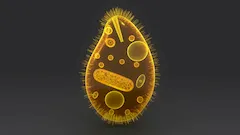

Balantidium coli

Balantidium coli to pierwotniak wywołujący chorobę zakaźna zwaną balantidiozą. Zakażenie tym pasożytem często występuje u świń. Człowiek zaraża się pierwotniakiem poprzez spożycie skażonego mięsa lub wody skażonej świńskimi odchodami, w której znajdują się cysty owego pasożyta. Możliwe jest też zakażenie w toaletach, kąpieliskach, poprzez brudne ręce, niedomyte warzywa i owoce, na drodze nietypowych aktywności seksualnych, poprzez bezpośredni kontakt z osobą zakażoną. Cysty, które doprowadzają do infekcji, przedostają się do przewodu pokarmowego i uwalniają trofozoity. Trofozoity namnażają się w jelicie grubym.